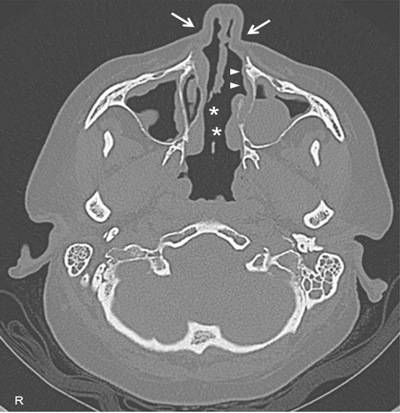

Figure 3

High-resolution computed tomography of paranasal sinuses, axial projection, showing a perforation of the nasal septum (asterisks), the absence of the anterior half of the left inferior turbinate (white arrows), and the atrophy of the upper lateral cartilages (white arrowheads).